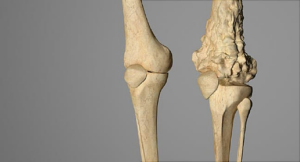

سرطان استخوان چیست؟ سرطان زمانی شروع میشود که سلولها شروع به رشد خارج از کنترل می کنند. سلولها تقریبا در هر بخشی از بدن میتوانند

سرطانهای اولیه استخوان (نمای کلی و انواع آن) اگر سرطان استخوان برای شما تشخیص دادهشده است یا در مورد آن نگران هستید، احتمالاً سوالات زیادی

جراحی برای سرطان استخوان جراحی، بخش مهمی از درمان اکثر انواع سرطانهای استخوان میباشد. معمولا شامل موارد زیر است: بیوپسی برای تشخیص سرطان برداشتن تومور